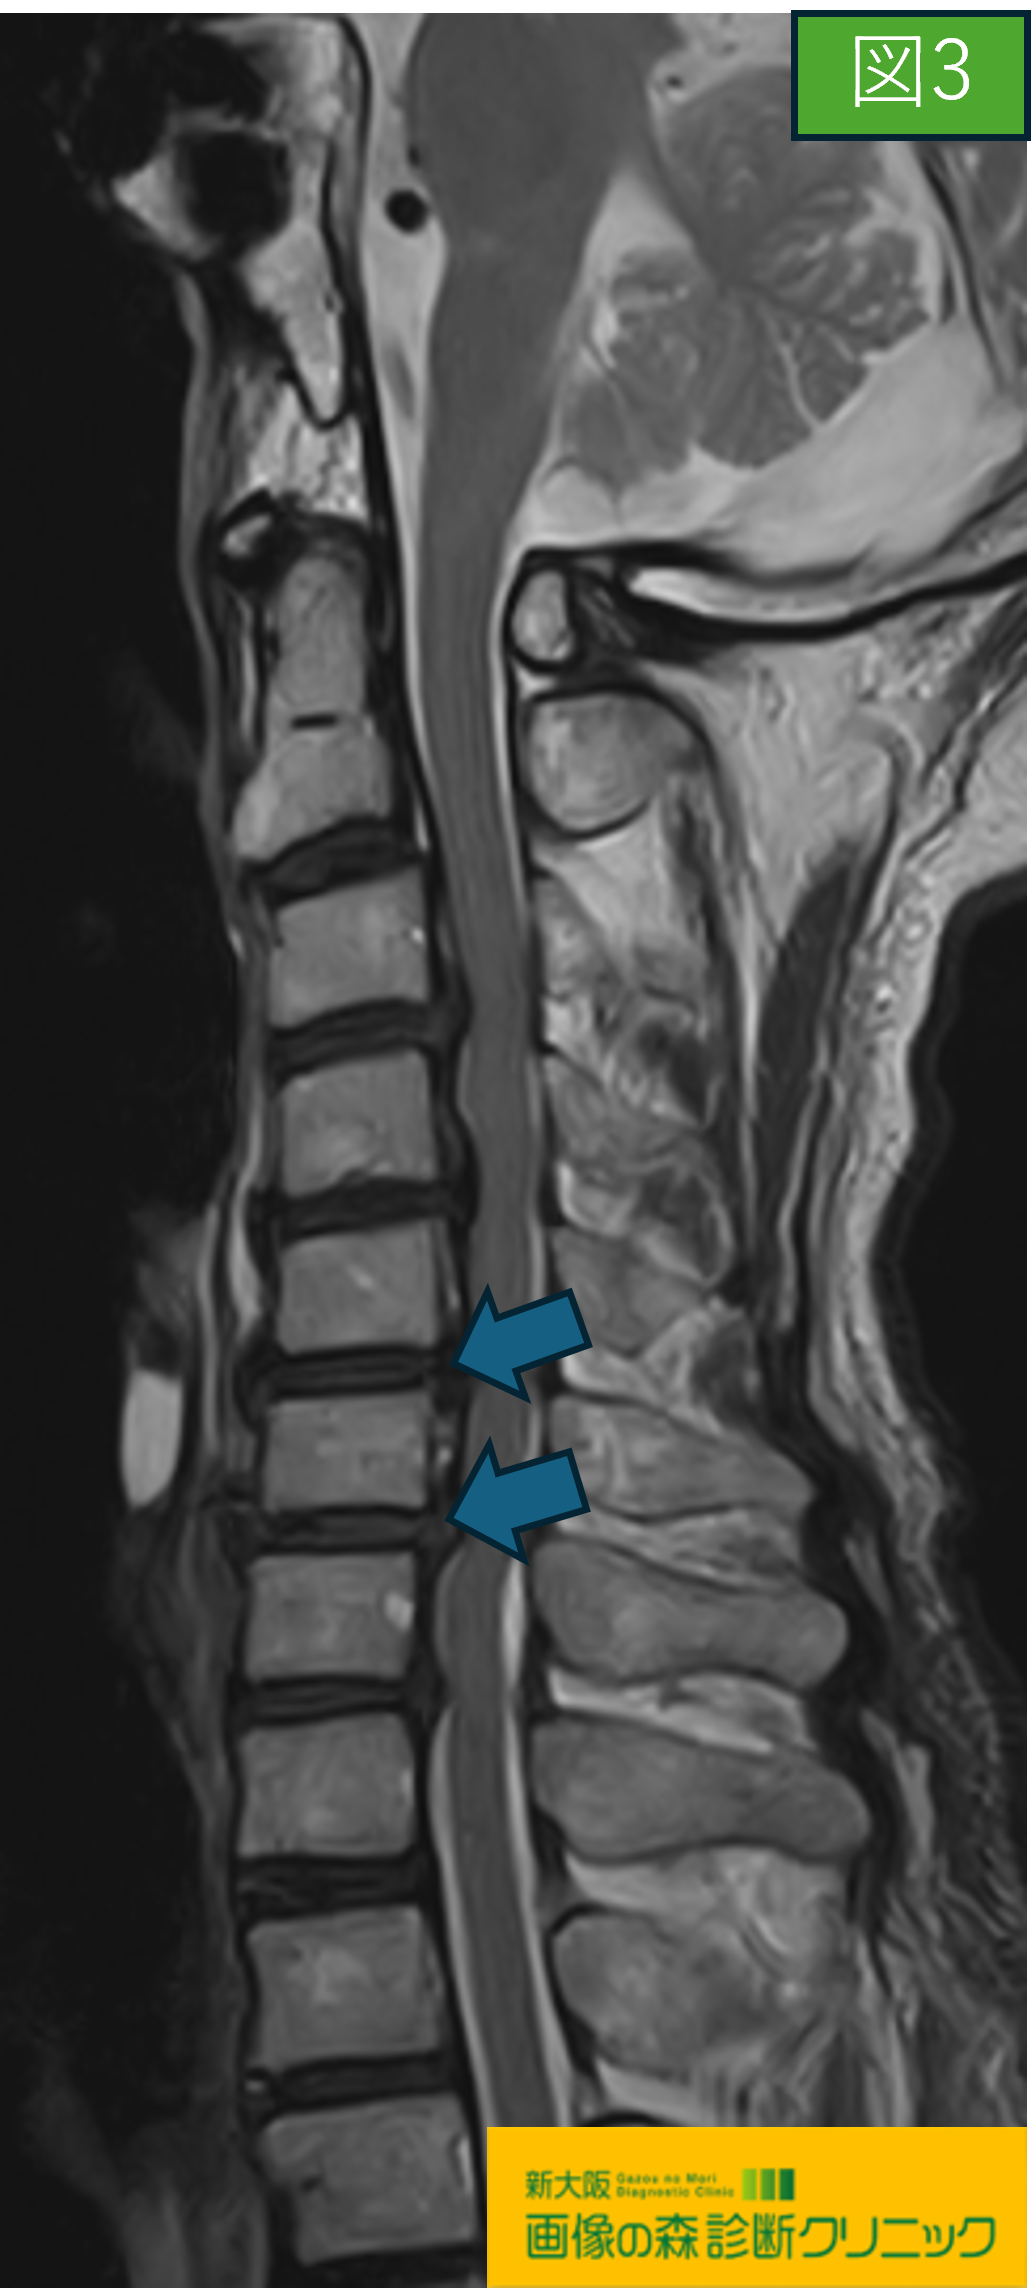

図3・図4では頚椎MRI画像で、どちらも

後縦靭帯骨化症(OPLL)の症例です。

図3の頚椎MRI画像では、肥厚した後縦靱帯が低信号(黒く)描出されます